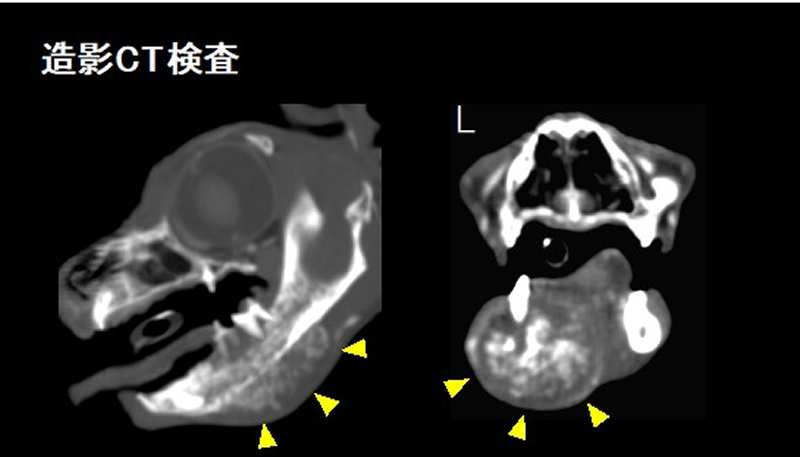

左下顎に発生した扁平上皮癌の造影CT画像